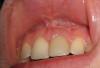

В 20 лет встал вопрос эстетики. Зуб потемнел. На фото моя лучезарная улыбка омрачнена темным зубом как ложка дегтя. Мне посоветовали оч хорошего частнопрактикующего врача. Так вот посмотрев снимок и собственно зуб резюмировал: безметалловая коронка. Винир отсек сразу(зуб этот на 70% видимой части пломба). На тот момент время не позволяло ставить коронку. Врач предложил внуризубное отбеливание. В 2 этапа закладывал состав( если я не ошибаюсь на основе пербората). И о чудо!!! Зуб побелел!!!

Сейчас мне 21 год. Я прилагаю снимки зубов. Первый 2005 год(до резекции), второй 2008 год. Фото улыбки 30 мин назад)

Посоветуйте, пожалуйста, где в Москве могупомочь с моей проблемой. Хочу оба передних зуба сделать однинаковыми по цвету. Знаю техначески это оч сложно, поэтому нужен опытный специалист. Еще хотела бы проконсультироваться по поводу отбеливания остальных субов( цвет эмали желтоватый).